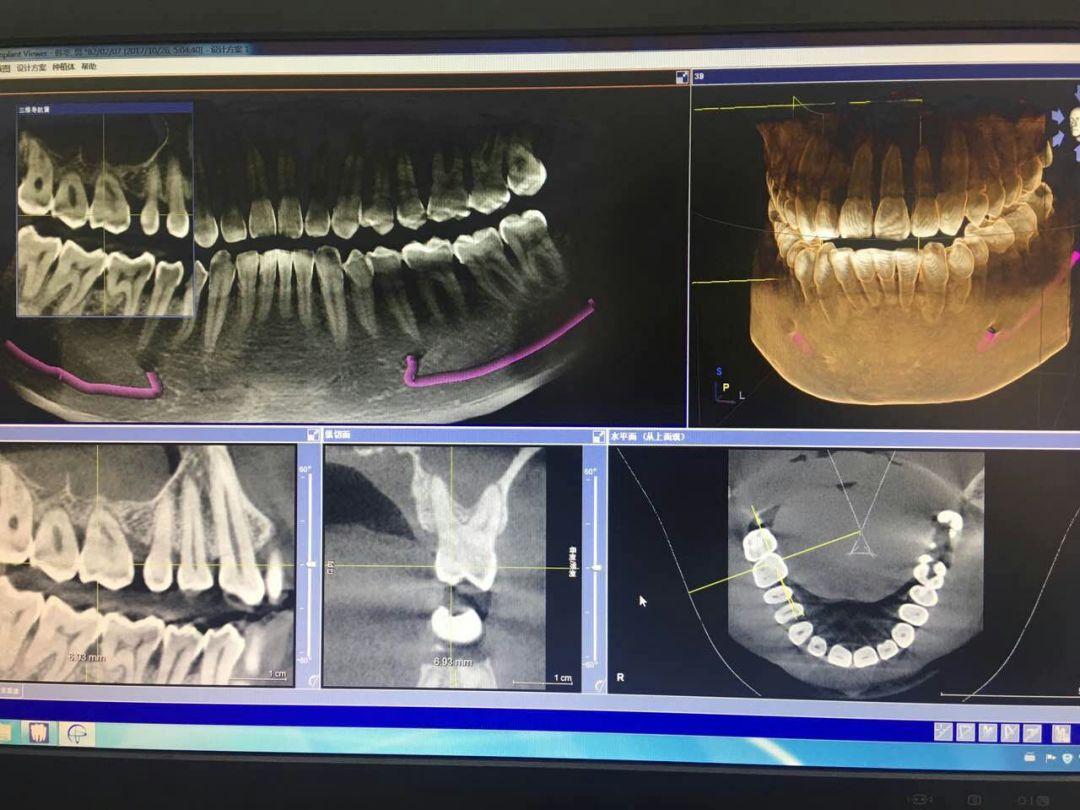

CBCT掃描可準確分析頜骨植入區(qū)的骨質、骨量、骨密度及植體與下頜神經管、上頜竇的關系,臨床醫(yī)生可以在圖像上模擬種植,直接與患者進行溝通及交流,并可指導手術者在手術方案中避開危險區(qū)域,手術的性。此外,臨床醫(yī)生還可以利用CT數據進行數字模型重建,配合軟件預先做好手術模板使種植手術更快捷。